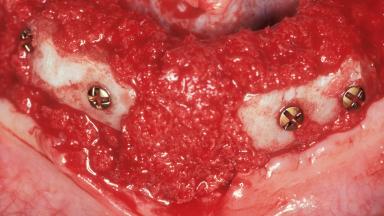

Horizontal Augmentation with Iliac Bone Grafts in the Treatment of Non-Syndromic Oligodontia

A 20-year-old woman was referred for implant therapy in 2004. Her medical history revealed no significant findings, and neither did she smoke nor take any medications. An extraoral examination revealed no abnormalities of the skin, hair or nails. The intraoral examination revealed only 11 permanent teeth clinically. These were normal in shape, size, and color. In addition, eight retained deciduous teeth (53, 62, 63, 71, 72, 73, 81, 82) were present. No abnormalities were detected during the general examination. The family history revealed that the patient’s father and two sisters were on record with similar conditions. The clinical examination revealed a thick gingival biotype. No recession of the attached gingiva was noted, but the retained deciduous teeth were mobile and unsightly. As a syndrome had not been diagnosed, the case was categorized as non-syndromic oligodontia.